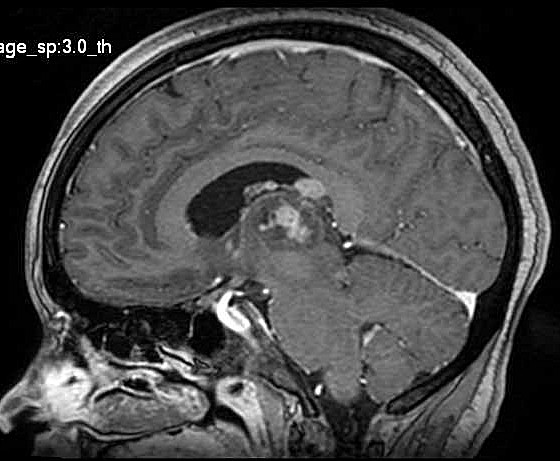

| Fem. 17a. |

| Nódulo sólido homogêneo preenchendo o III ventrículo, com limites precisos, com hipossinal em T1 e hipersinal em T2 e FLAIR, que se impregna por contraste paramagnético. Lesão menor implantada no assoalho do IV ventrículo provavelmente representa disseminação por via liquórica. |

| F. 17a. Tumor teratóide rabdóide atípico de III ventrículo. RM | HE | VIM, GFAP | HHF35, desmina, 1A4 | AE1AE3, EMA |